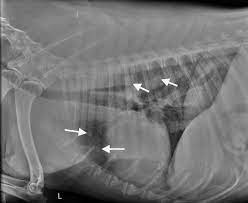

Secondary Lung Cancer Dogs Trained Dogs Can Identify Lung Cancer Study Shows The Second Type Is from 4.bp.blogspot.com Primary lung tumors are cancers that arise in the lung tissue of both dogs and cats. Canine lung cancer is almost always considered to be secondary in nature. General cancer symptoms in dogs. Lung cancer in dogs can be primary or metastatic. Lung cancer in dogs is serious, but it is treatable. Types of lung carcinoma in dogs. Lung cancer is the leading cancer killer in both men and women in the u.s. As these masses continue to grow uncontrollably (often at undetermined and varying rates), they may also begin to spread (metastasize) to other locations via the blood or lymphatic system.

Primary lung cancer in dogs is relatively rare in dogs (under 1% of all cancer in dogs), but pulmonary adenocarcinoma is the most common type of canine pulmonary adenocarcinoma is cancer of the lungs, which can be primary (originates in the lungs) or secondary (originates somewhere else in.

As these masses continue to grow uncontrollably (often at undetermined and varying rates), they may also begin to spread (metastasize) to other locations via the blood or lymphatic system. General cancer symptoms in dogs. Lung cancer in dogs is serious, but it is treatable. In 1987, it surpassed breast cancer to become the leading cause of cancer deaths in women.1. Primary lung tumors are cancers that arise in the lung tissue of both dogs and cats. What is the life expectancy? Cancer is the leading cause of death in dogs. Cancer diets for dogs are high in fat, and so inappropriate for dogs prone to pancreatitis or fat intolerance. They are rare in both species, but slightly more common in dogs. Dogs symptoms and canine health. Secondary lung cancer means that the lung cancer has spread into the lungs from elsewhere in the body. Canine lung cancer is almost always considered to be secondary in nature. Metastatic lung cancer is the most common form of lung cancer in dogs and unfortunately dogs who are diagnosed with this secondary form of cancer have less chance to recover from this disease than dogs diagnosed with primary lung cancer.